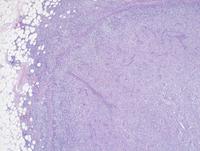

H&E images of AITL

Low, medium and high power images showing replacement of the lymph node architecture by a hypervascular background and atypical lymphoid infiltrate extending into the perinodal adipose tissues. At higher power, the lymphoid infiltrate comprises polymorphous cellular composition including medium sized clear atypical cells associated with background lymphocytes, histiocytes and plasma cells.